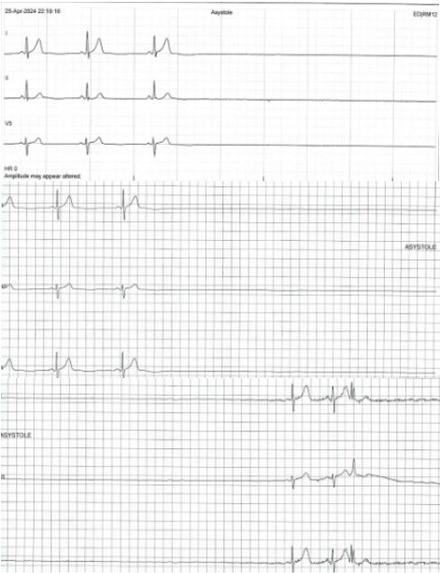

Case: A 66-year-old male presented after experiencing two episodes of syncope. He denied any prodromal or anginal symptoms. His medications included propranolol 10 mg twice daily for essential tremors. He had no family history of unexplained syncope or sudden cardiac death. He was hemodynamically stable and had one episode of fever at 102°F. Telemetry recording showed vagal-mediated sinus arrest and pauses without escape. Blood work showed normal cell counts, electrolytes, thyroid-stimulating hormone, and erythrocyte sedimentation rate, with a slightly elevated C-reactive protein of 22.2 mg/L. He tested positive for COVID-19 and had negative Lyme and Ehrlichia serologies.

Decision Making: Due to symptomatic long sinus pauses, propranolol was discontinued, and he received a temporary pacemaker set at 50 beats per minute (bpm). He had another syncopal episode while being paced at 50 bpm, suggesting a neurocardiogenic mechanism, so the pacing rate was increased to 70 bpm. An echocardiogram showed a normal ejection fraction without any significant valvular disease. The syncope was determined to be vasovagal due to autonomic dysfunction in the setting of COVID-19. After 72 hours without further syncope, the temporary pacemaker was removed, and he was discharged home with an implantable loop recorder (ILR). A one-month follow-up showed no syncope, and ILR interrogation showed no bradycardia or pauses.

Conclusion: Neurocardiogenic syncope with prolonged asystole and sinus pauses is an uncommon presentation of COVID-19 infection. The clinical course of autonomic dysfunction following COVID-19 is not very clear, and monitoring with an ILR is reasonable before considering permanent pacemaker implantation.